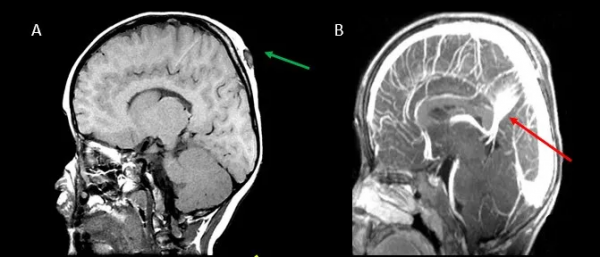

生長性骨折:又稱軟腦膜囊腫,是顱骨骨折的晚期創傷後併發症,其表現為腦脊液或腦實質突出到皮下組織,隨後骨折擴大。在隨後的研究中,CT 顯示為擴大的骨折,MRI 可以識別骨缺損及其內容物

軸位骨窗 CT 顯示額骨右側骨折,在 6 個月後骨折間隔增寬。另一名患者在軸位 T2WI 和 FLAIR 上顯示骨質缺損,額骨上充滿囊性病變(黃色箭頭)